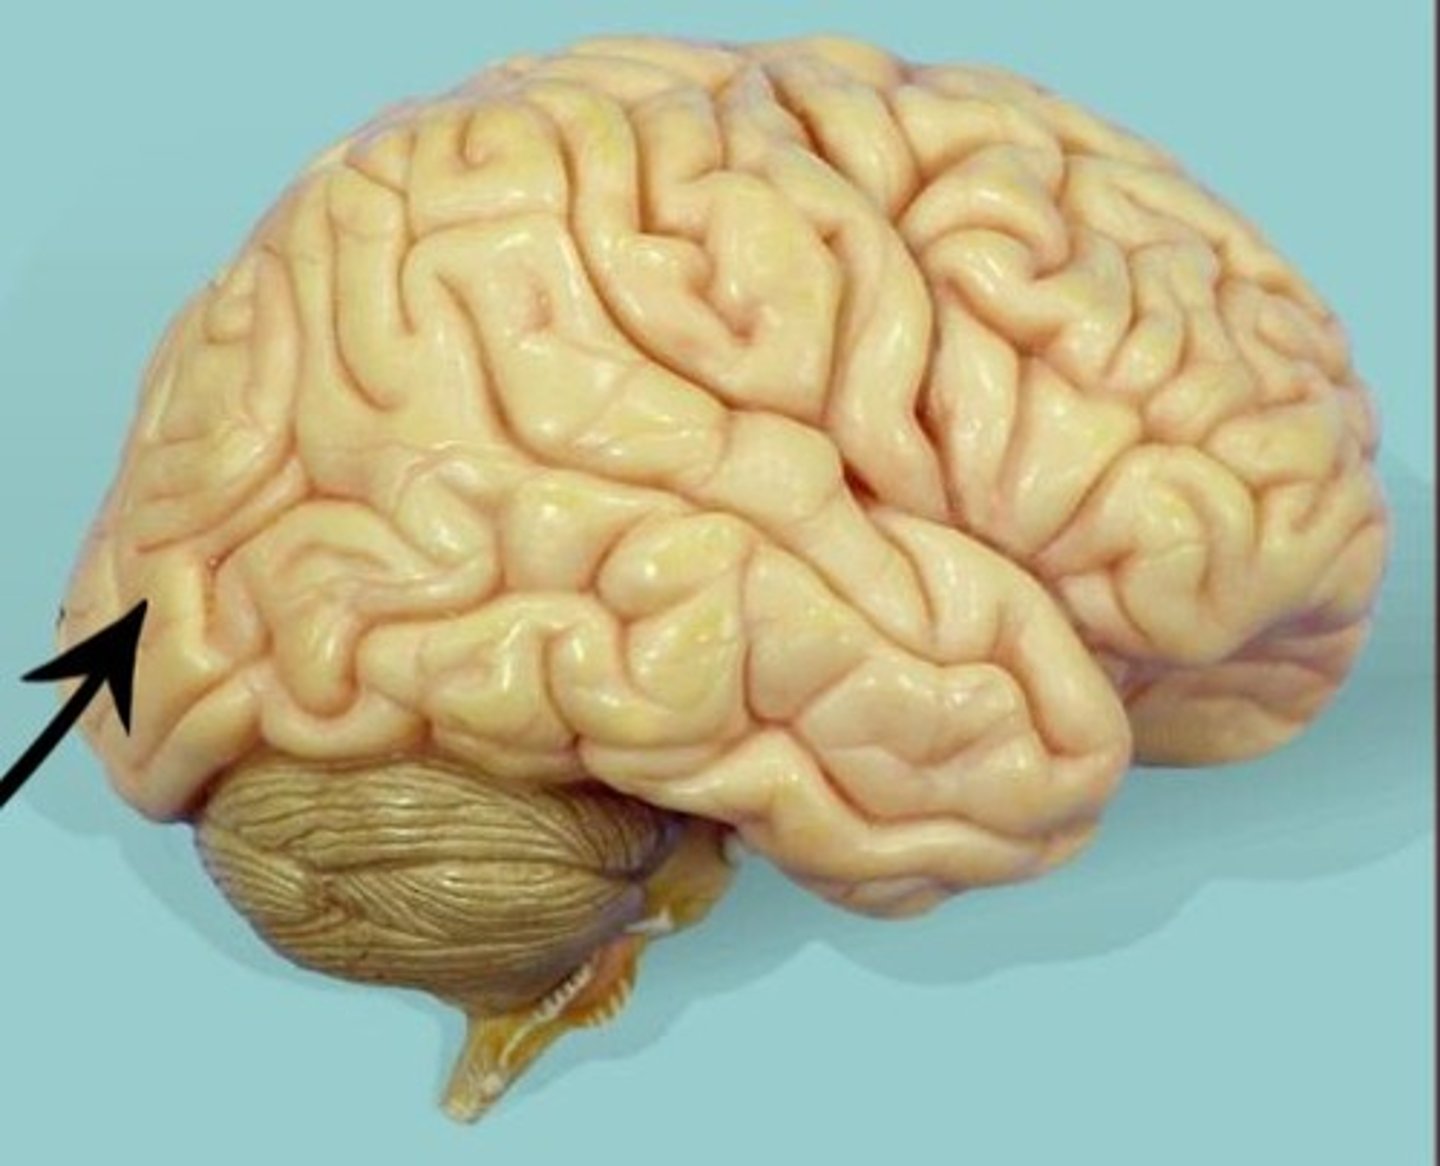

gyrus

folds in the brain (blue arrow)